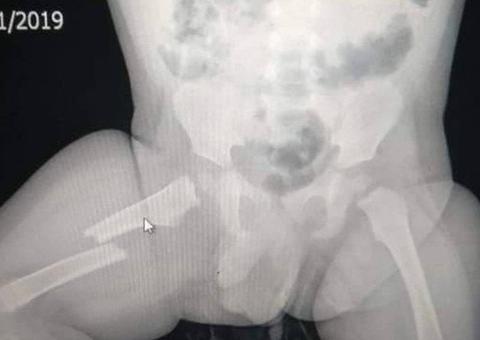

Ao avistar a polícia, um dos suspeito tentou fugir em um veículo modelo Montana de cor vermelha. O condutor atirou em direção aos policiais da Rocam e, na perseguição, acabou batendo em um muro. O homem então abordado e com ele encontradas uma arma de fogo de fabricação caseira um cartucho calibre 36, e 60 trouxinhas de entorpecentes oxi e pasta base.